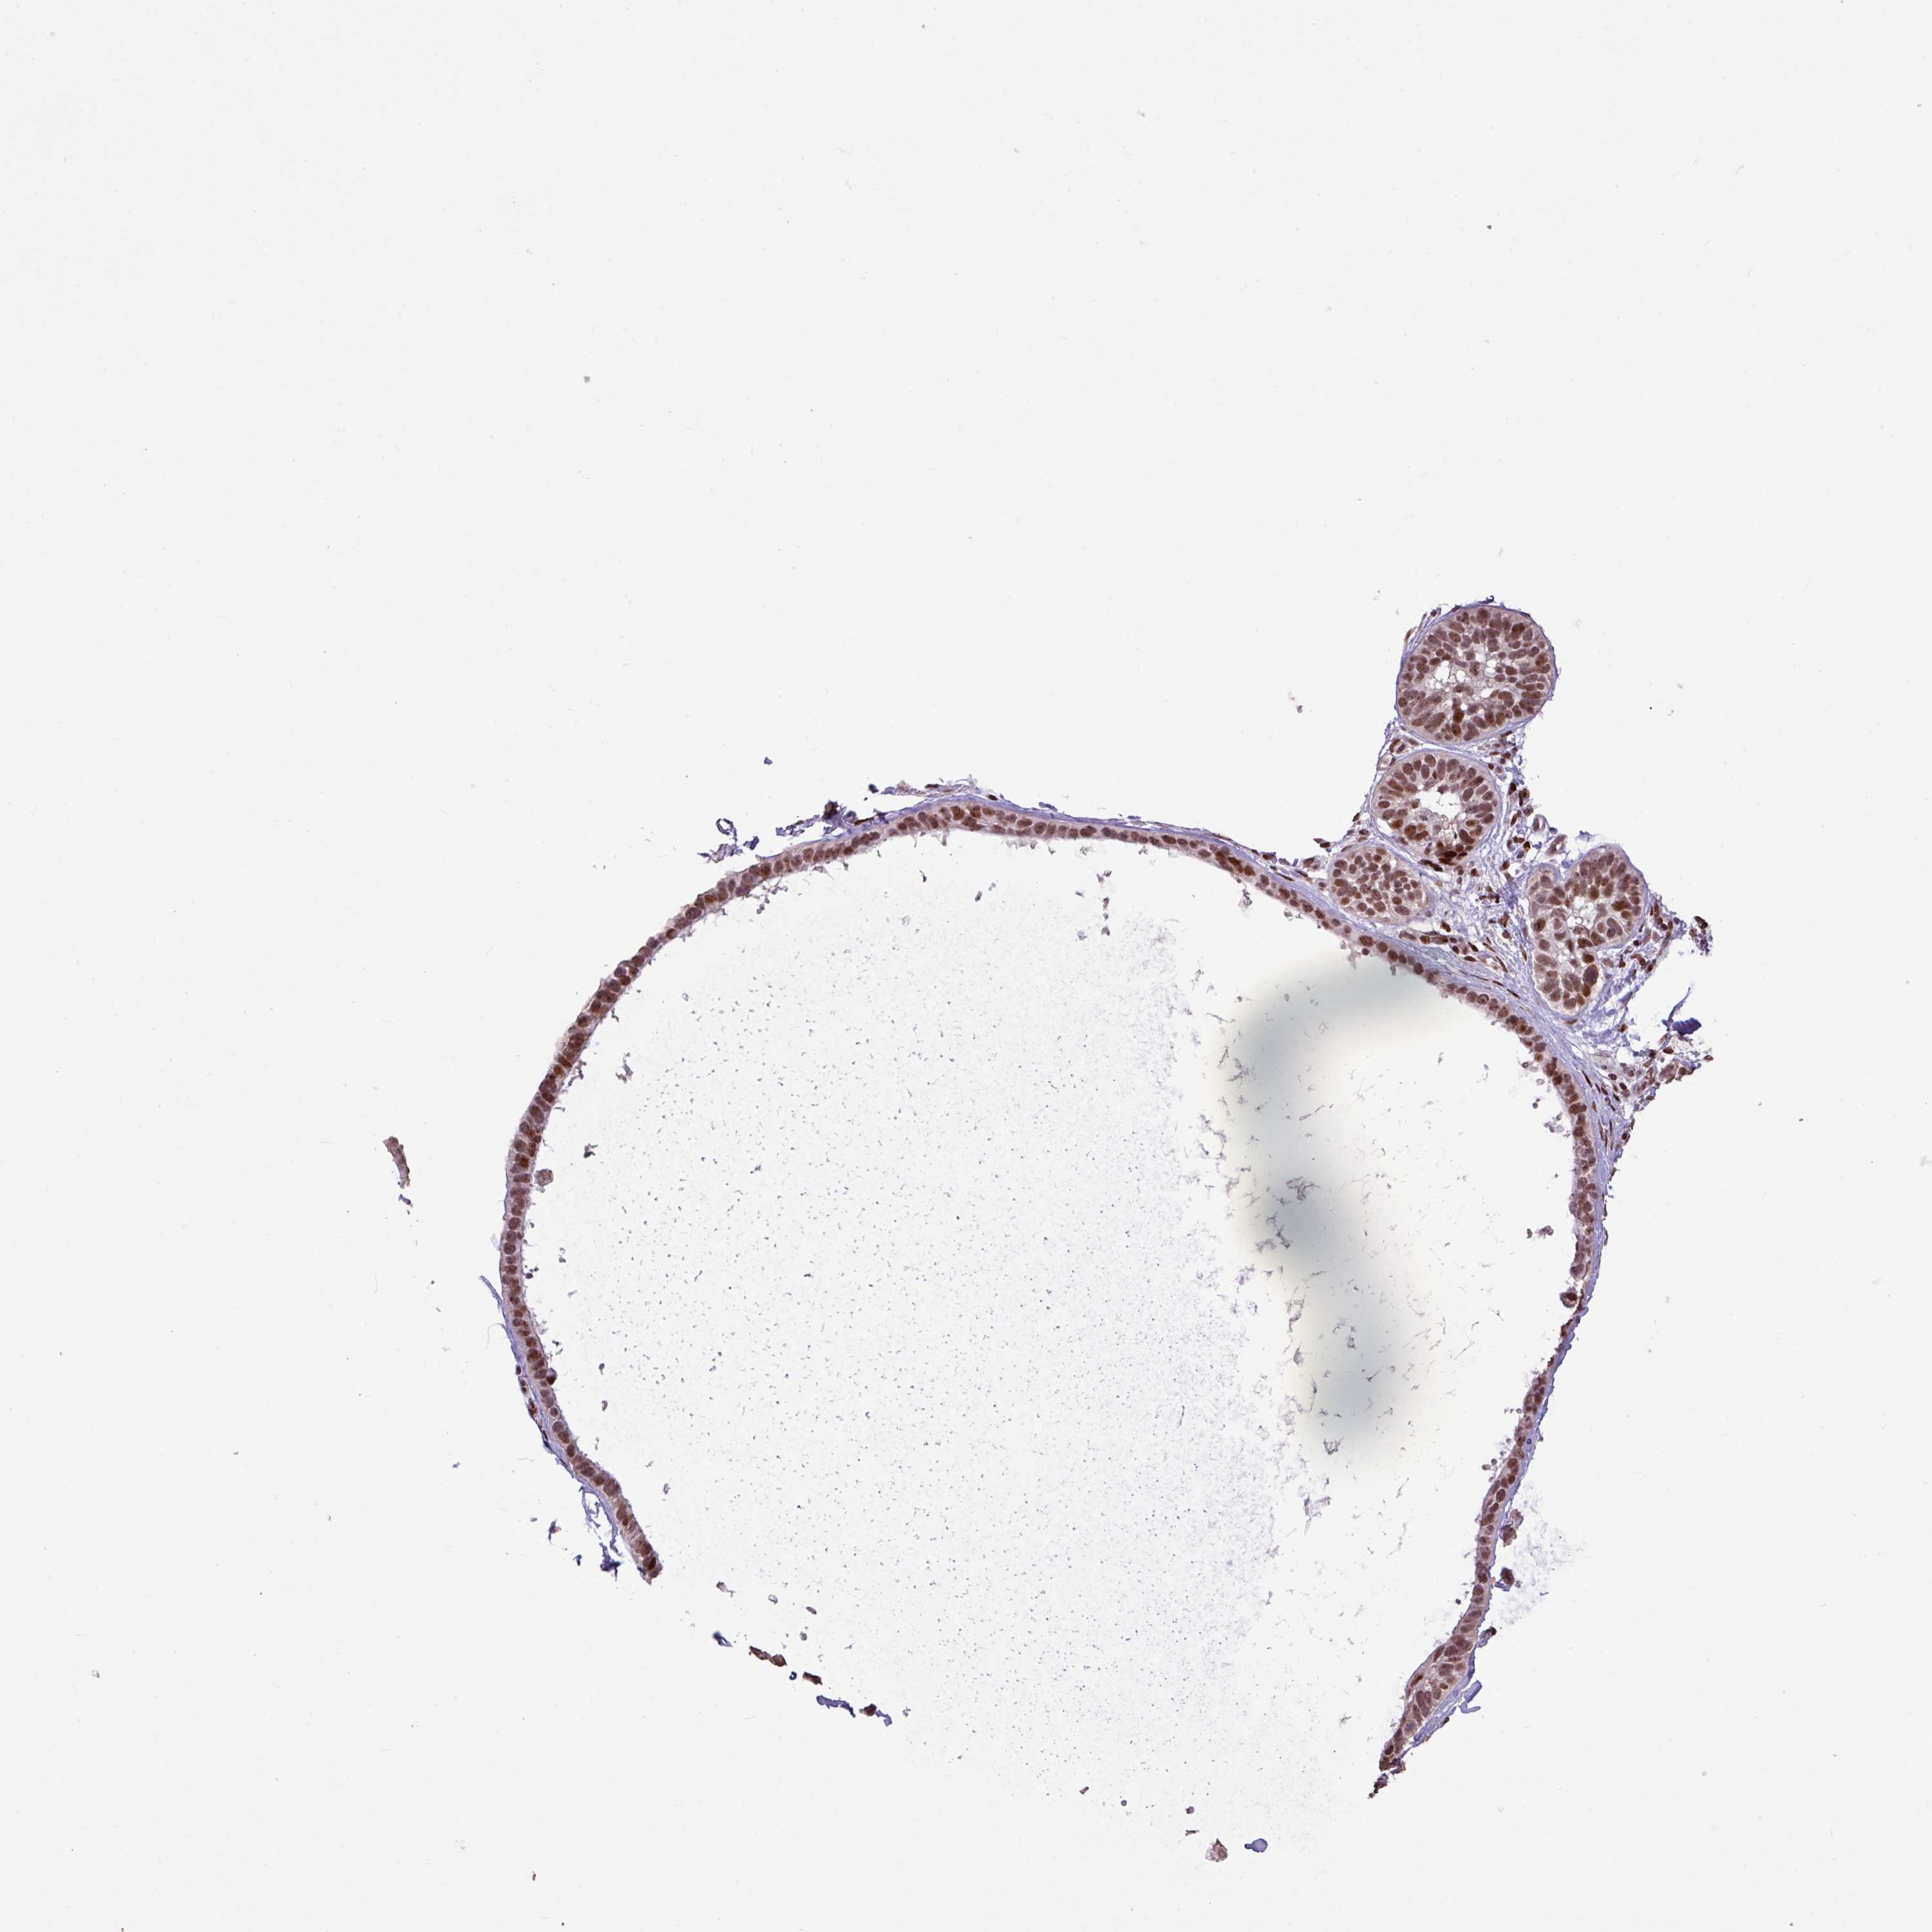

Basal cell and squamous cell cancer

SKIN CANCER - Protein expressioni

A mouse-over function shows sample information and annotation data. Click on an image to view it in a full screen mode. Samples can be filtered based on level of antibody staining by selecting one or several of the following categories: high, medium, low and not detected. The assay and annotation is described here.

Antibody HPA053153

Basal cell carcinoma